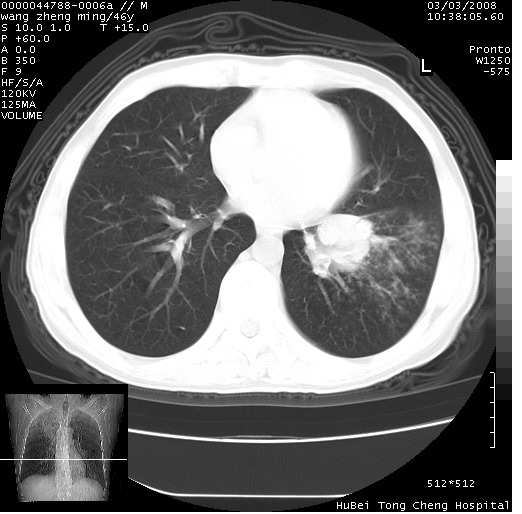

以下是引用卜一在2008-3-22 1:37:00的发言:[br]右肺实质性肿块,边缘不整,明显见毛刺征 分叶征及胸膜凹陷征,右上叶支气管明显变窄,远端散在的片状 斑片状实变影。另:左肺门较大肿块,支气管受累 变窄,远侧见阻塞性肺炎。纵隔内见肿大淋巴结。多考虑:右肺周围性肺癌伴左肺门 纵隔淋巴结转移!